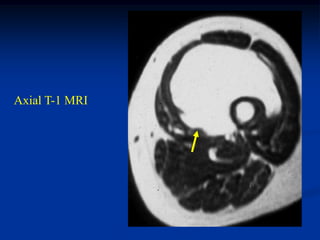

Case #1199

30 year male with

myxoid liposarcoma

posterior thigh

Axial T-1 MRI

Case #1199 30 yearmale with myxoid liposarcoma posterior thigh Sagittal T-1 MRI